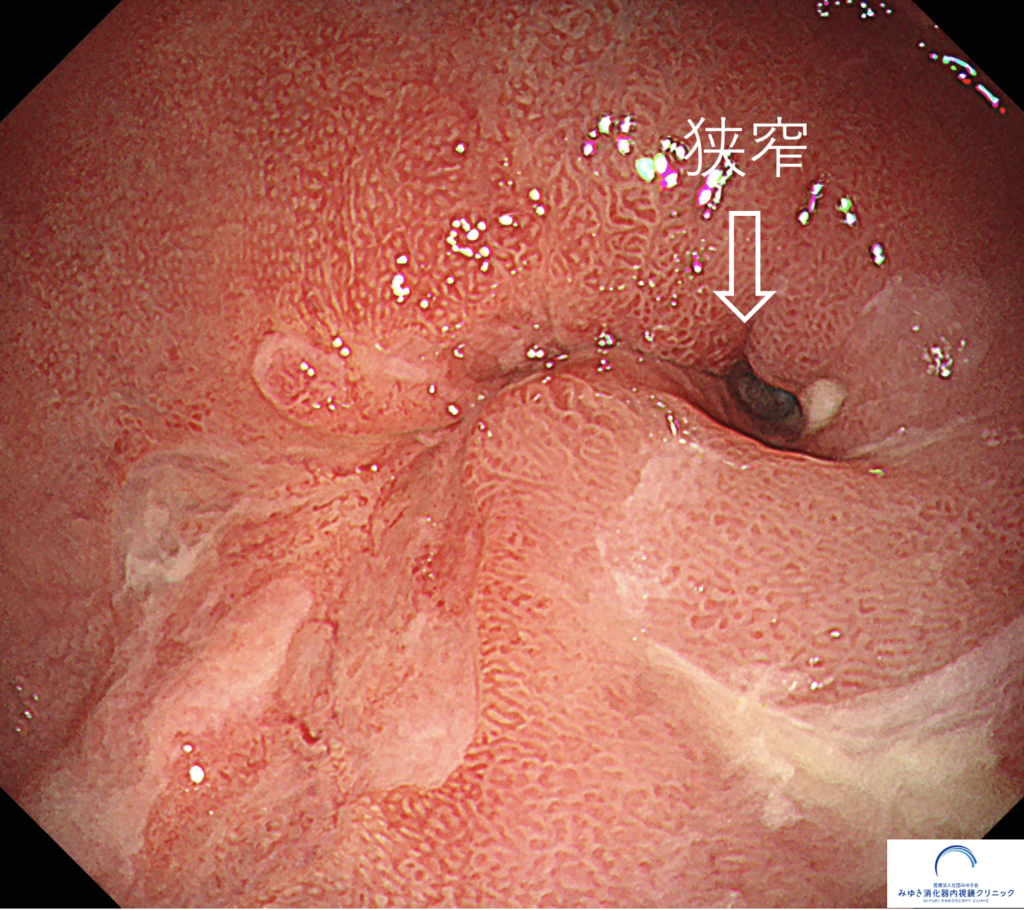

食事が胸につかえるため、胃カメラを行ったところ、食道が細くなっていました(狭窄)。狭窄部手前からの生検でバレット食道がんと診断されたため、ロボット手術をしていただきました。